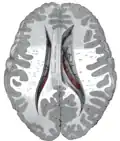

![]() Caudate nucleus (in red) shown within the brain | |

Transverse cut of brain (horizontal section), basal ganglia is blue | |